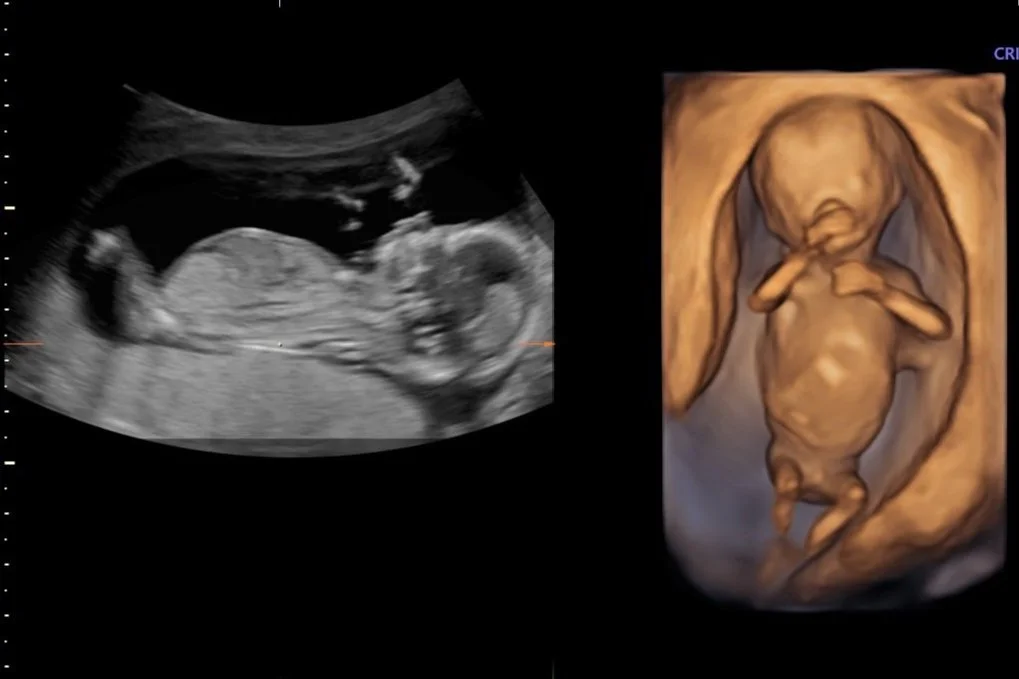

For the best results, we recommend scheduling your appointment as early in your pregnancy as possible to ensure that the procedure can be performed during the optimal timeframe. Use our Pregnancy Scan Calculator to determine the most suitable dates for your scan. Although a Nuchal Translucency scan or Early Anatomy Screening can be conducted between 12 to 14 weeks, we recommend scheduling this scan at 13 weeks. Our experienced sonographers have found that this specific timeframe allows for optimal visualization of your baby's development, including intricate structures such as the brain, heart, and kidneys. This small window of time can make a significant difference in the clarity and detail of the scan, providing valuable insights into your baby's well-being.

Our Nuchal Translucency Scans take up to 50 minutes and include:

- 2 x 3D thermal printed hard copy images

- All pictures taken on the day straight to your mobile phone